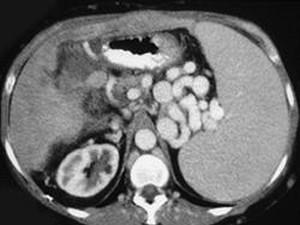

问题 男,50岁,患乙肝多年,现腹胀,右上腹痛,消化不良,消瘦、乏力、贫血、黄疸,血清转氨酶升高,白蛋白/球蛋白比值倒置。CT检查如下图,最可能的诊断是 ( )

选项 A.肝硬化、肝癌 B.肝硬化、腹膜后淋巴结肿大 C.肝硬化、肝癌、腹膜后淋巴结肿大 D.肝硬化、门脉曲张、脾大 E.肝硬化、脾大

答案 D